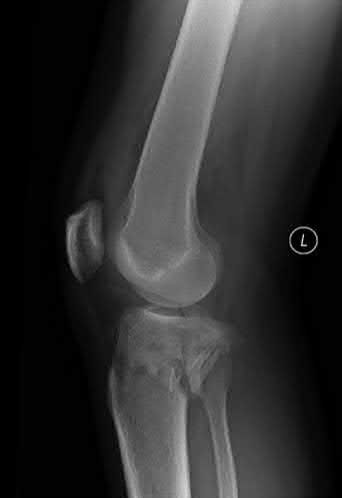

A 36-year-old male falls from a 10-ft scaffold and suffers the injuries shown in Figures A and B. The patient is placed in a spanning external fixator and brought back to the operating room once his soft tissues are amenable. Planning to use a dual-incision approach, what is the correct interval to use when approaching the medial side?

The posteromedial approach to the tibial plateau is between the the pes anserine tendons and the medial head of the gastrocnemius.

A dual-incision approach is often utilized to optimally place definitive fixation for bicondylar tibial plateau fractures. For fractures that require posterior or posteromedial fixation, the correct interval is between the pes anserine and the medial head of the gastrocnemius.

Figure A and B exhibit a bicondylar tibial plateau fracture with a posteromedial fragment noted on the lateral x-ray. Illustration A exhibits the surrounding anatomy and interval in between the medial head of the gastrocnemius and the pes anserine.